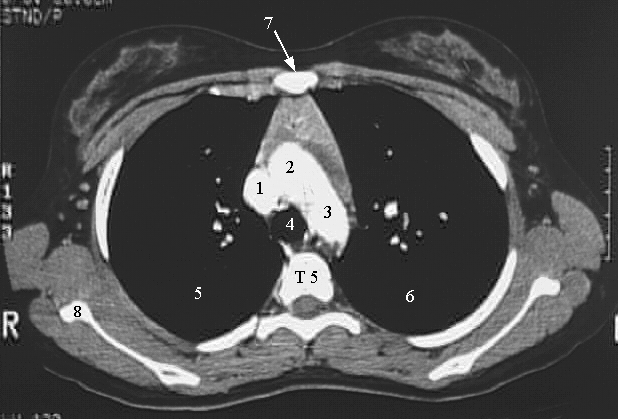

Thorax-Chest CT Great vessels

1. Superior vena cava

2. Ascending aorta

3. Descending aorta

4. Trachea

5. Right lung

6. Left lung

7. Sternum

8. Scapula